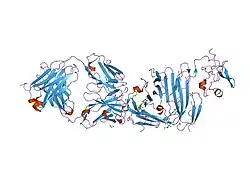

Urokinase is a 411-residue protein, consisting of three domains: the serine protease domain (consisting of residues 159–411), the kringle domain (consisting of residues 50-131), and the EGF-like domain (consisting of residues 1-49). The kringle domain and the serine protease domain are connected by an interdomain linker or connecting peptide (consisting of residues 132–158). Urokinase is synthesized as a zymogen form (prourokinase or single-chain urokinase), and is activated by proteolytic cleavage between Lys158 and Ile159. The two resulting chains are kept together by a disulfide bond between Cys148 and Cys279.[9]

The most important inhibitors of urokinase are the serpins plasminogen activator inhibitor-1 (PAI-1) and plasminogen activator inhibitor-2 (PAI-2), which inhibit the protease activity irreversibly. In the extracellular matrix, urokinase is tethered to the cell membrane by its interaction to the urokinase receptor.